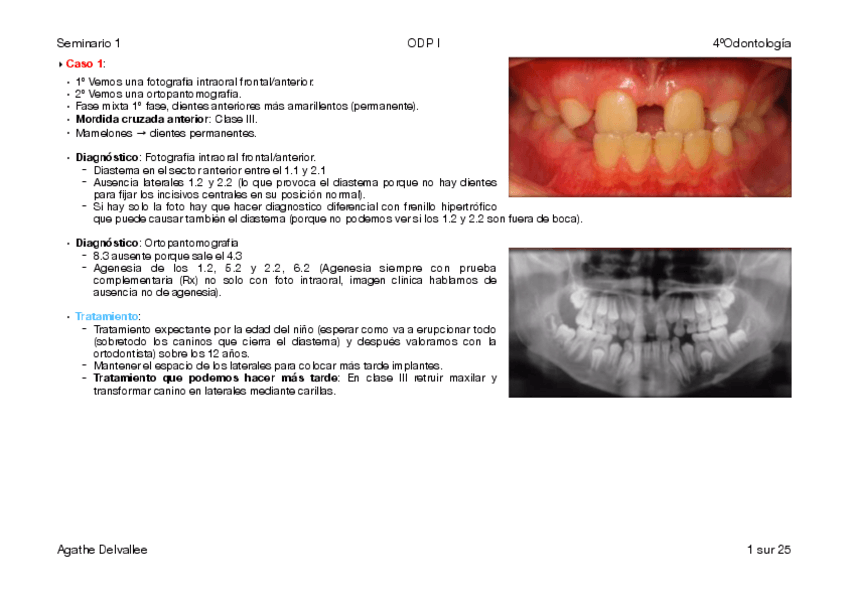

He publicado nuevos practicas de 4º Odontopediatría I: Seminario-1-ODP-I.pdf

25 páginas